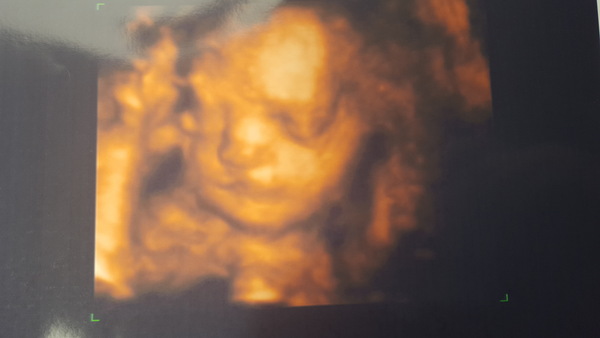

Lovely 4D scan though Grin

Lauren what a gorgeous 4D, she's a cutie.

Thanks indi very happy with the pics, wasn't a fan of 4d but I loved it when I was there

Gorgeous scan and name Lauren.

Lovely picture Lauren! That's so detailed. Love Jemima too.

Lauren that's a lovely scan! She is adorable - just look at that little nose! And I love the name Jemima!